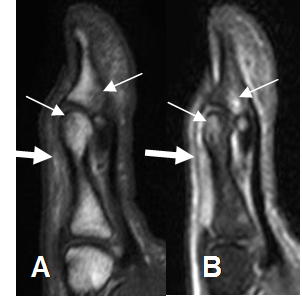

Fig 64. Lesión del mecanismo extensor.

A: RM sagital en T1 y B: RM sagital en STIR. Contusión del pulgar, con edema óseo de la cabeza de la falange proximal y la base de la distal. (Flechas delgadas). Hay cambios inflamatorios rodeando el tendón extensor, el cual permanece integro. (Flecha gruesa).